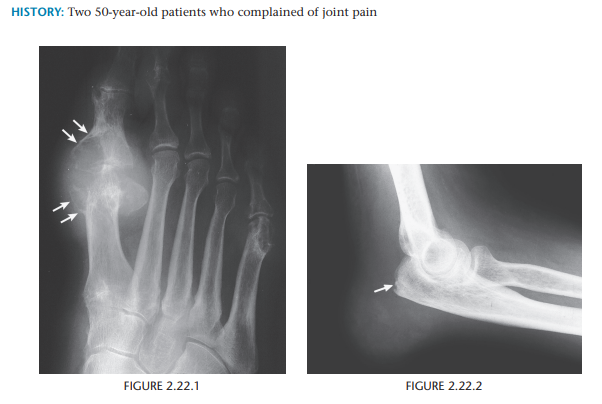

Gout

Erosions with sclerotic borders and overhanging margins with preservation of the articular space + soft tissue swelling

Most common bursa - olecranon

Bilateral - indication of gout